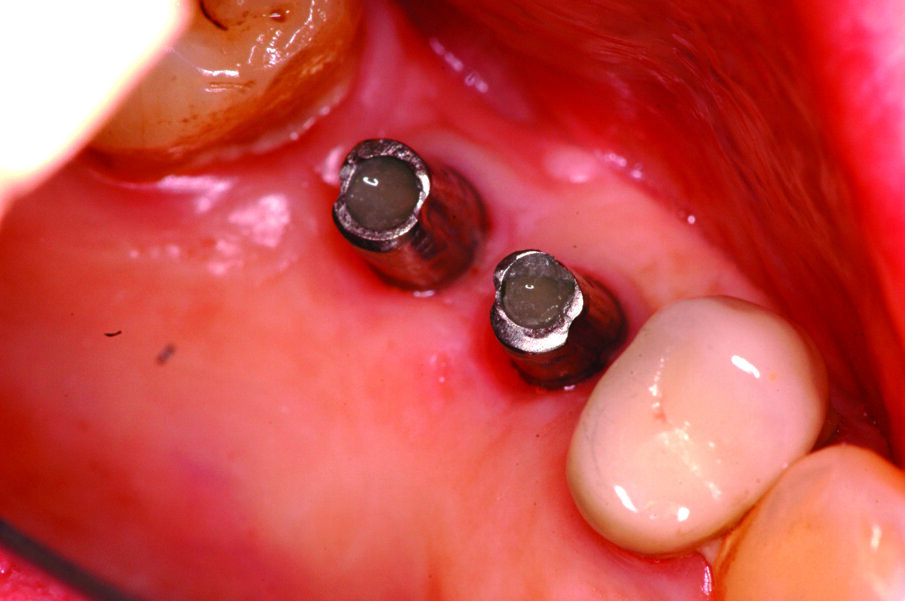

Una volta eseguito il disegno dell’antrostomia (Fig. 5), si procede al sollevamento della membrana con tecnica manuale (Figg. 6, 7) e all’iniziale inserimento di biomateriale granulare 0,5-1 mm (AlphaBio’s Graft, Alpha-Bio Tec, Israele). La corticale viene lasciata integra e aderente alla mucosa schneideriana in modo da diventare il futuro pavimento dell’antro (Fig. 8), anche per supportare il collasso della membrana durante il periodo di guarigione. A protezione della stessa è inserita una spugnetta di collagene equino (Condress, Smith&Nephew, UK). Contestualmente si procede con l’inserimento di due impianti autofilettanti SPI 3.75 x 13 mm (Alpha-Bio Tec, Israele) (Figg. 9, 10) e, al termine, viene ultimato il riempimento con biomateriale (Fig. 11). L’antrostomia viene poi coperta con una membrana riassorbibile 15 x 20 (AlphaBio’s Graft, Alpha-Bio Tec, Israele) e il lembo viene passivato e suturato con due linee di sutura 5-0: una a materassaio orizzontale e l’altra con punti staccati (Vicryl, Ethicon, USA) (Fig. 12). La paziente viene dimessa con la seguente terapia farmacologica: amoxicillina cpr 1 gr (1 cpr ogni 12h per 6 giorni), Prednisone cpr 25 mg (2 cpr per due giorni a scalare) per il controllo dell’edema post-operatorio e sciacqui con clorexidina 0.2% dal giorno successivo (1 sciacquo al giorno per 15 gg). Le suture sono rimosse a 15 giorni e la paziente è inserita in un programma di recall a cinque settimane per gestire eventuali complicanze durante la maturazione dell’innesto. Viene eseguito il secondo tempo chirurgico dopo 6 mesi e, verificata l’avvenuta osteointegrazione degli impianti, vengono rilevate le impronte e il caso è finalizzato con due corone unite in metallo ceramica (Figg. 13-15). Al termine della riabilitazione, visto il buon mantenimento igienico, la paziente viene inserita in un programma di follow-up a sei mesi (Figg. 16, 17).

Fig. 9_Fasi dell’osteotomia implantare.

Fig. 10_Particolare dell’iniziale riempimento del seno mascellare e dell’inserimento implantare.

Figg. 13-15_Particolari dei monconi in titanio e delle corone in metallo ceramica.